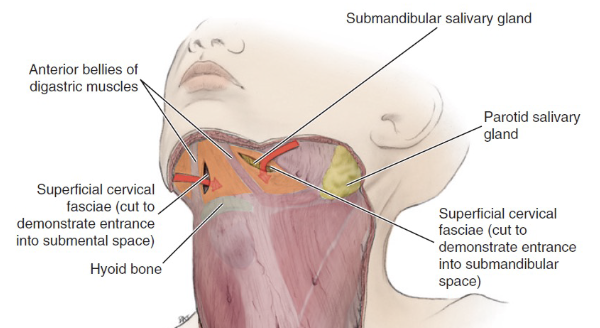

Fasciae

Superficial fascia

- 表情肌

- Platysma

Deep fascia

Head

- Temporal fascia

- Temporal arch以上

- Masseteric-parotid fascia

- Temporal arch以上

- 連到investing fascia

- Buccopharyngeal fascial

- 連到investing fascia

- Pterygoid fascia

- Pterygoid m. 外

Neck

-

Investing fascia

- 最外層

-

Carotid fascia

-

Visceral fascia

- 食道呼吸道

-

Vertebral facial

Space

Submental & Submandibular space

Submental

- Digastric, Hyoid bone, Mandibular symphysis 為界

- Superficial cervical fascia為底,Mylohyoid m. 為頂